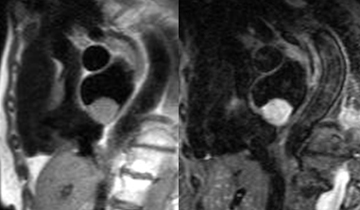

Envahissement tumoral de la paroi latérale du VG avec hypersignal T2 (séquence STIR) et hypersignal post-gadolinium (PSIR) chez un patient de 49 ans aux antécédents de séminome une quinzaine d’année auparavant avec récidive l’année précédente, traitée par chimiothérapie et extension sous forme de nodules pulmonaires et de métastase cérébrale traitée par radiothérapie. La paroi latérale infiltrée est hypokinétique avec FEVG abaissée à 54%.